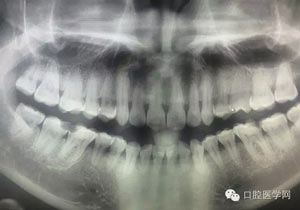

病例1:患者迫切希望保留自己的這一顆牙齒,根尖周陰影比較大,二度松動.而且旁邊有種植修復(fù)體,和患者溝通好后,治療好后觀察一個月后冠修復(fù),因為有種植的后期修復(fù),所以有了機會觀察,術(shù)后三個月和術(shù)后四個月,根尖恢復(fù)的還算不錯,希望能夠繼續(xù)觀察下去.這樣子的病例,做的時候我們一定要非常的小心,和患者要有充分的溝通以及不同科室的溝通然后決定怎么樣做比較好,假如就是出現(xiàn)了問題,到時候我們也比較好處理些,免得我們自己到時候不好收場。